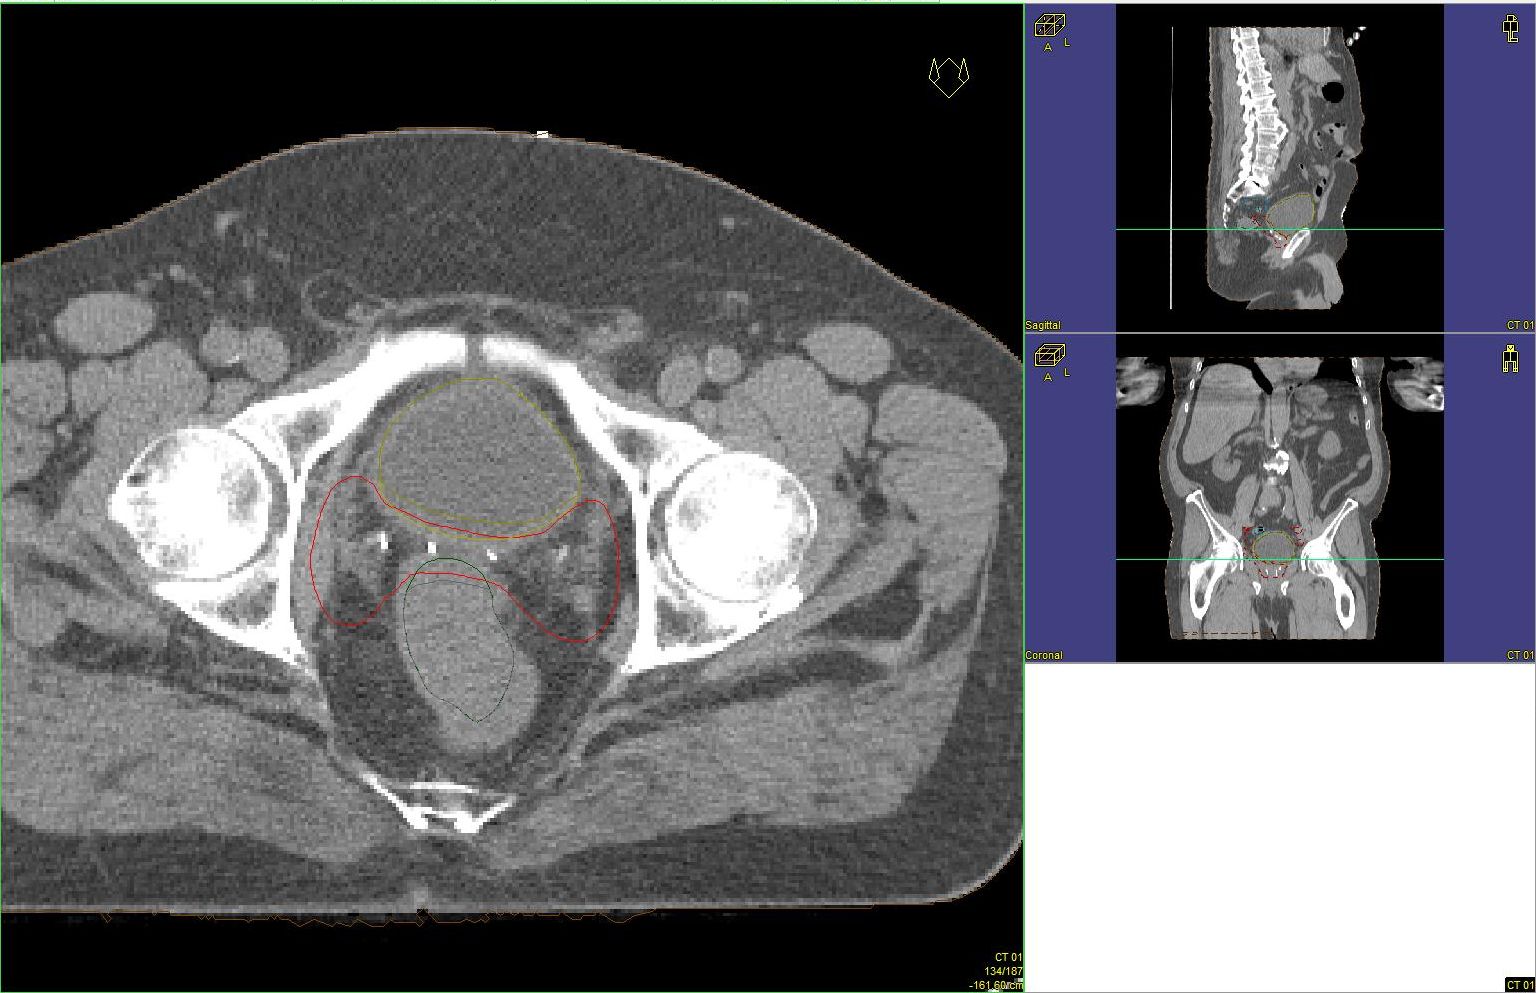

Prostata-Ca: Zielvolumen der postoperativen Radiotherapie

Beispiel: postoperative RT